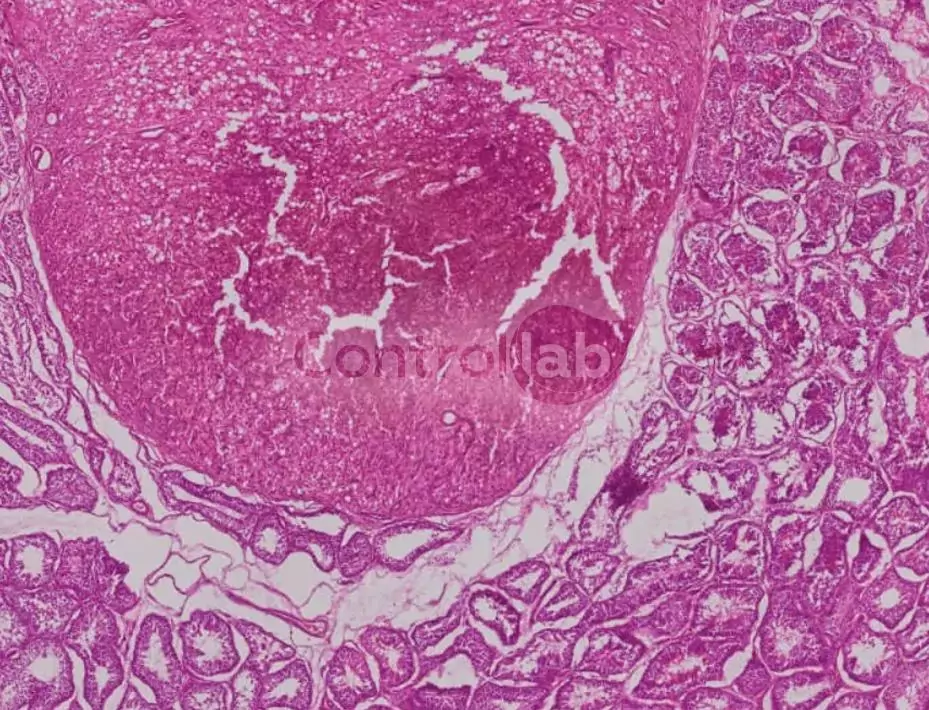

Pathological Anatomy

- Pathological Anatomy

Proficiency Testing

- Digitized cases of hematoxylin and eosin-stained slides prepared from animal biopsy material (dogs and cats).

- Pathology (3 items x 4 rounds) – EPPAV | EP208